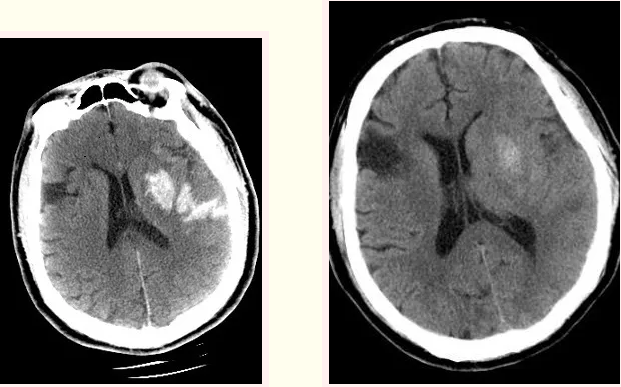

术后即刻复查头部CT造影剂外渗情况和术后24h复查头CT造影剂明显吸收

经过精心的治疗,朱大爷出院了。目前,病人可以自己走路,虽言语仍笨拙,但继续康复训练可逐渐恢复。